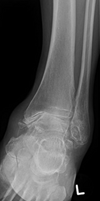

17

Q

correction

A

needs slightly more internal rotation